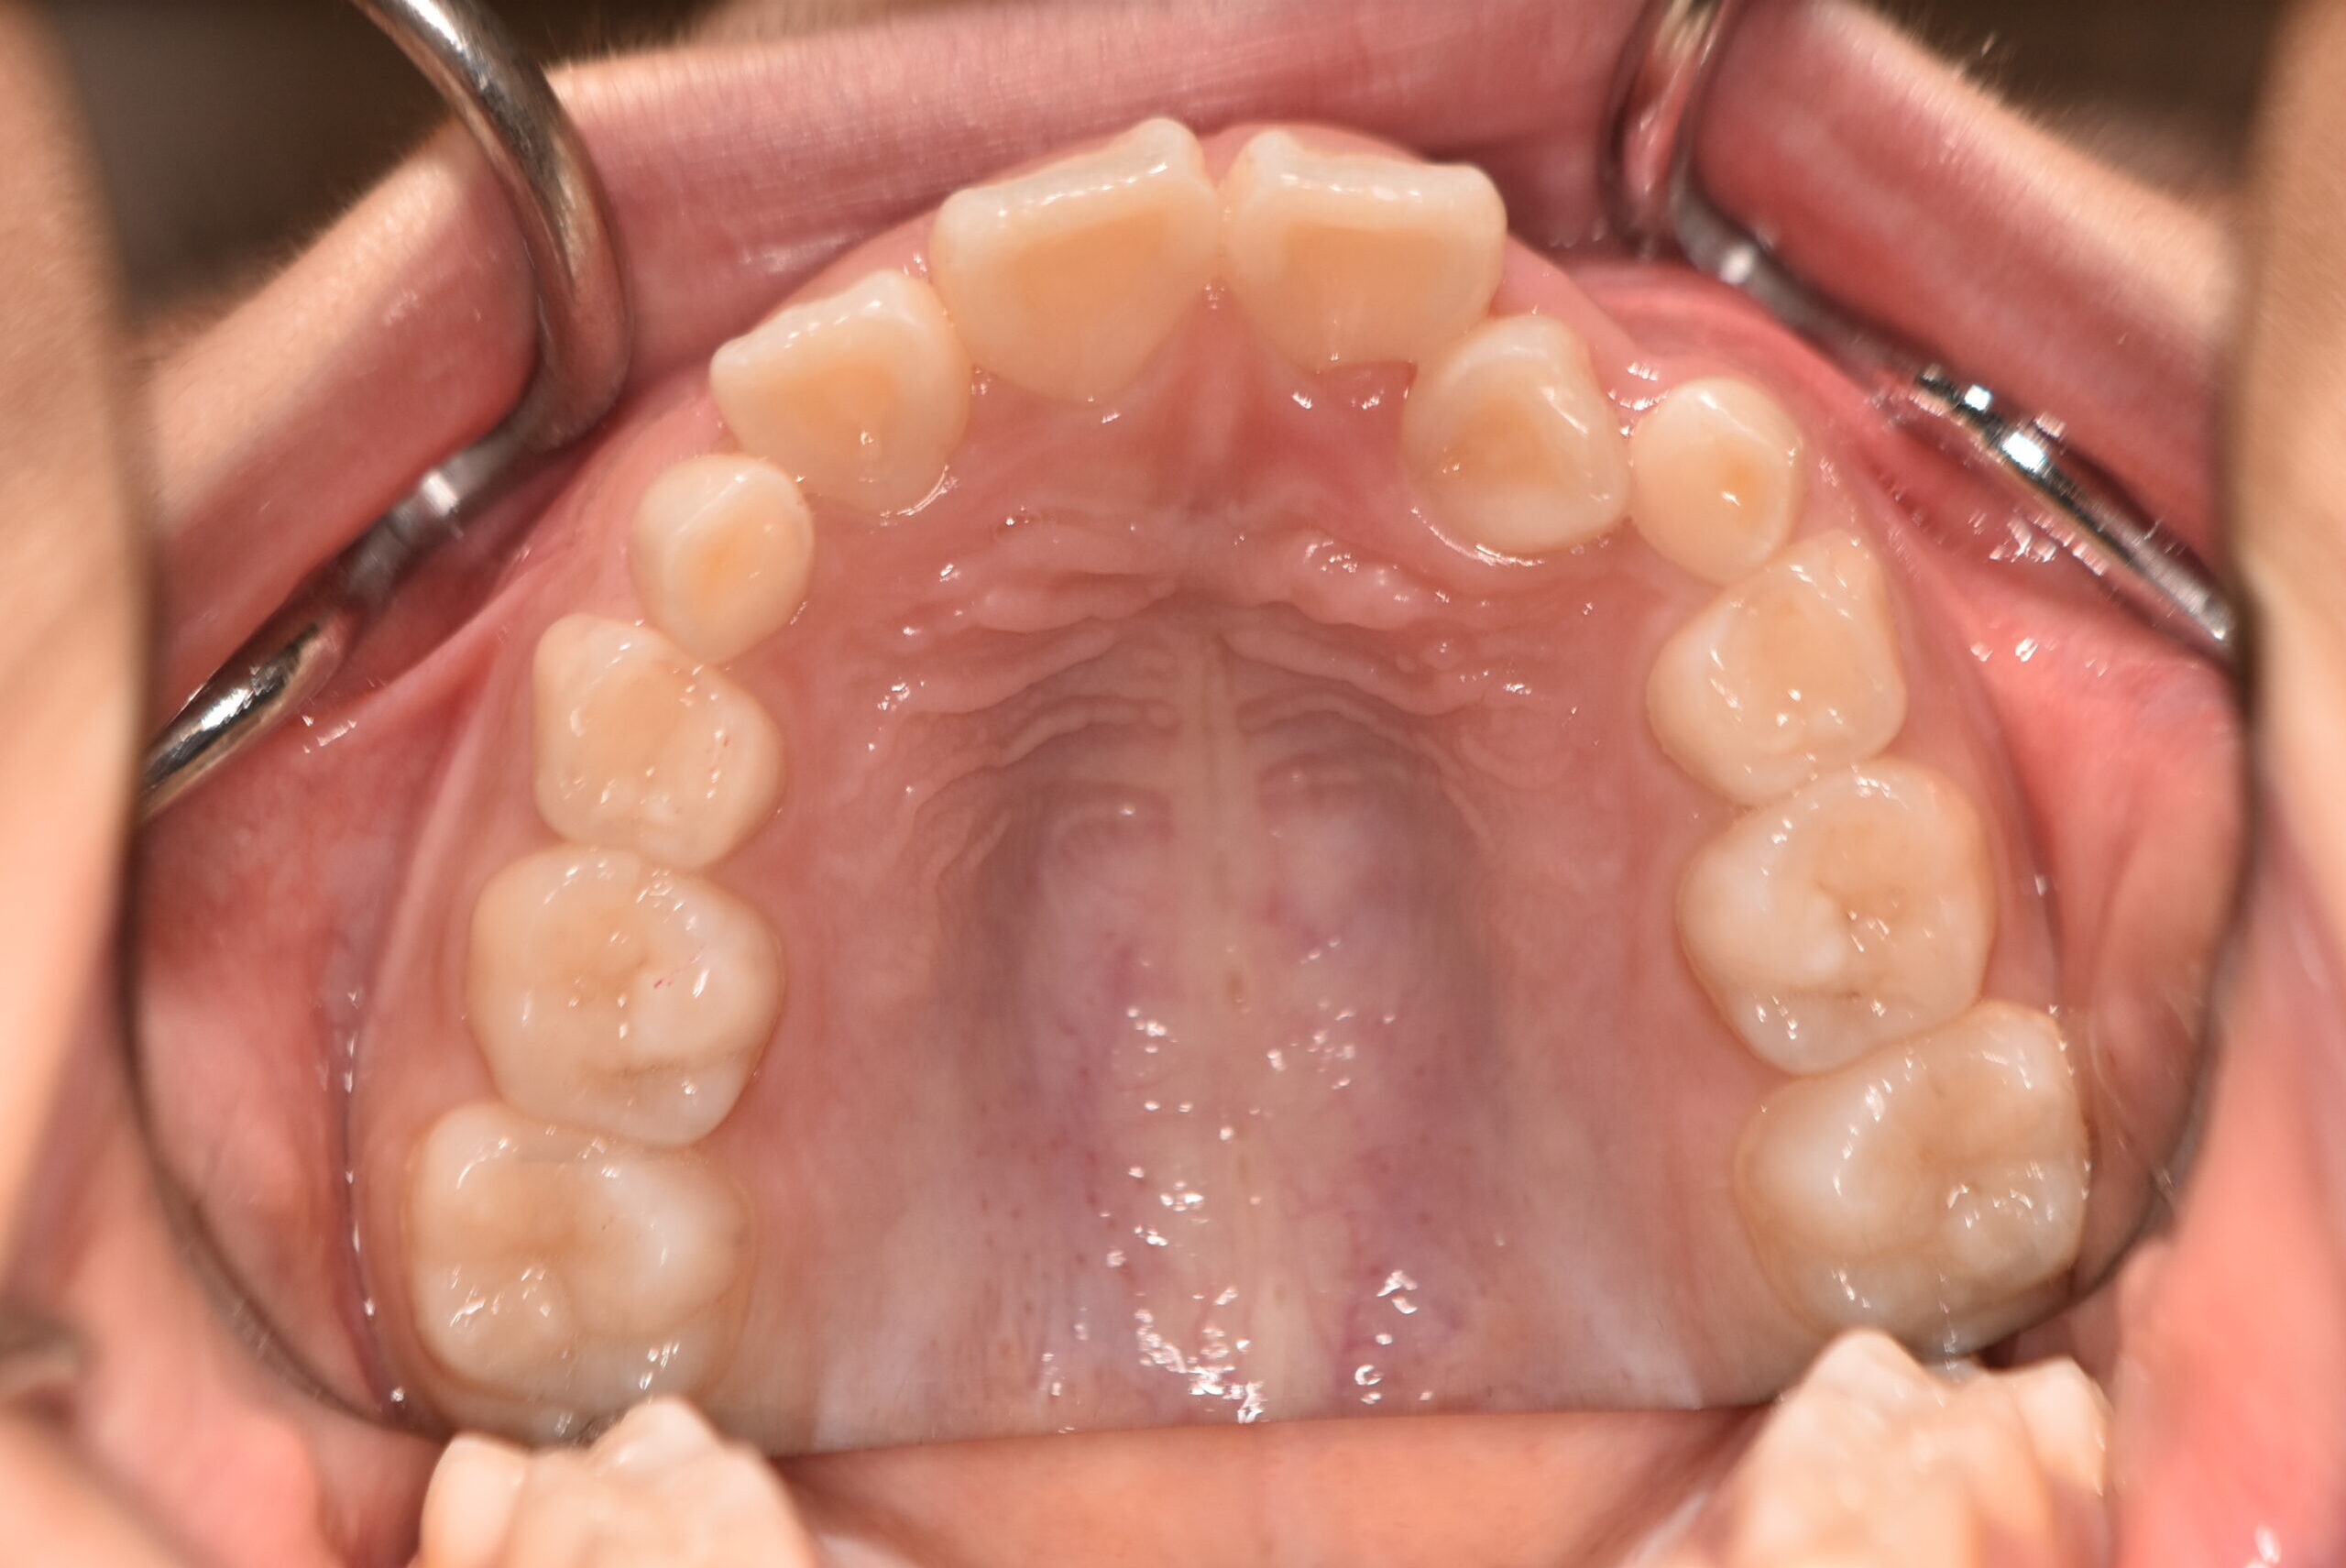

| 治療内容の詳細 | 初診時7歳の女児で、歯のがたつきを気にされ来院されました。 検査の結果、前歯部叢生を伴うアングルⅡ級不正咬合と診断しました。 治療としてはマウスピース矯正(インビザラインファースト)で配列を行い、上下顎の側方拡大と萌出スペースを確保しました。 治療期間は、1年でした。 今後、側方歯生え変わりまで経過観察を行います。 |